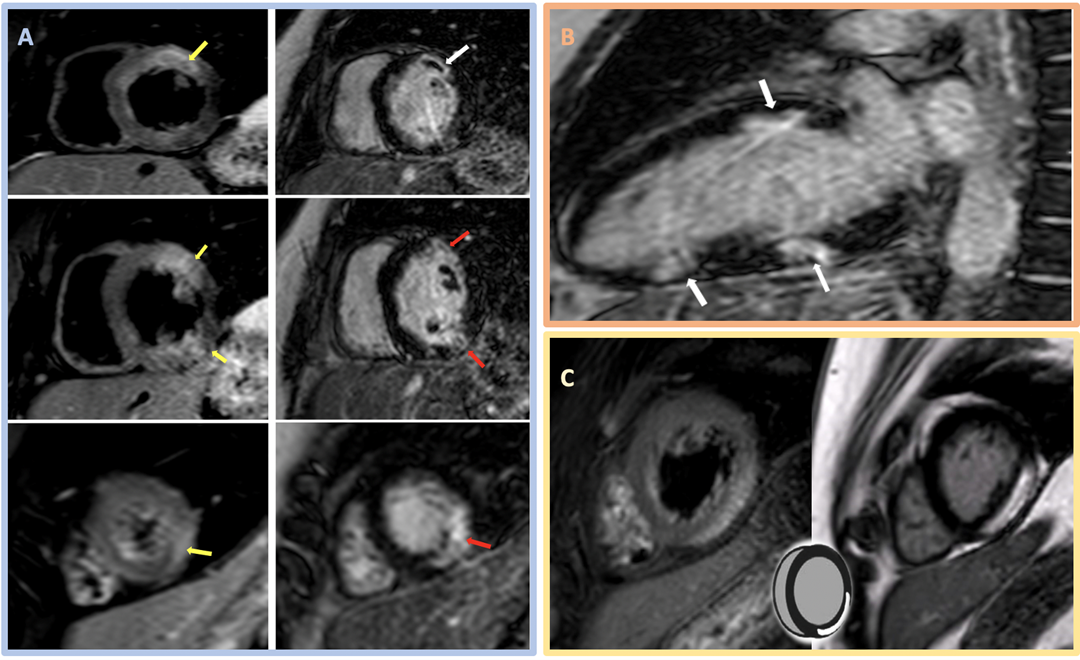

Image 2: CMR Images Showing Regional Myocardial Edema, LGE, MVO, and Myocarditis

(Panel A) CMR images in the SAX orientation (base-mid-apical) with T2-weighted images demonstrating regional myocardial edema (yellow arrow) on the left and the corresponding LGE (red arrow) and MVO depicted as a central dark core inside the bright scarred area (white arrow) on the right; these findings suggest acute/subacute MI. (Panel B) CMR LGE (white arrow) in a 2Ch orientation. (Panel C) Example of the classic appearance of myocarditis by CMR.

2Ch = two-chamber; CMR = cardiac magnetic resonance; LGE = late gadolinium enhancement; MI = myocardial infarction; MVO = microvascular obstruction; SAX = short-axis.

In this case, CMR had findings of normal BiV size with preserved BiV function (LVEF 56% and right ventricular ejection fraction 54%). Tissue characterization revealed areas of myocardial edema (hyperintensity on T2-weighted images; panel A in Image 2) and subendocardial late gadolinium enhancement (LGE) in a multifocal distribution along the anterior midventricular segment, inferior midventricular segment, inferior apical segment, and lateral apical segment. Microvascular obstruction (dark area within the core of LGE uptake) was also evident, predominantly in the anterior segments (panels A and B in Image 2). These findings are consistent with MINOCA, with coronary embolism as the most plausible mechanism in the setting of APS. Hence, the importance of managing underlying connective tissue disorder and avoiding or minimizing anticoagulation interruptions was emphasized. The patient was discharged on apixaban and did not have any further events on follow-up.

Although chest discomfort with pleuritic features, lack of definitive ECG ischemic changes, and underlying connective tissue disorder would raise the possibility of myopericarditis, available evidence is insufficient to secure such diagnoses and initiate treatment. CMR is useful when suspecting myocarditis or any other MINOCA mimics. Myocarditis CMR features include a nonischemic injury with LGE that affects epicardial or midmyocardial regions (sparing the subendocardium) and does not follow vascular territories (panel C in Image 2).2,3